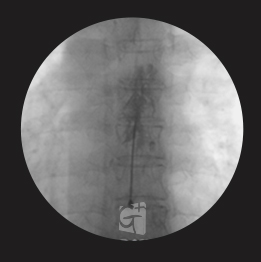

경추 신경성형술

-

경추 좌측 2번 신경절

경막외 카테터 삽입 -

척추관 안쪽으로 진입하여 약물 주입

-

원인부위 염증 제거 및 유착 박리

-

유착박리로 추간공 확보 신경 압박 감소

-

척추관에서 약물이 퍼져나오는 모습

-

목 신경 전체를 효과적으로 치료